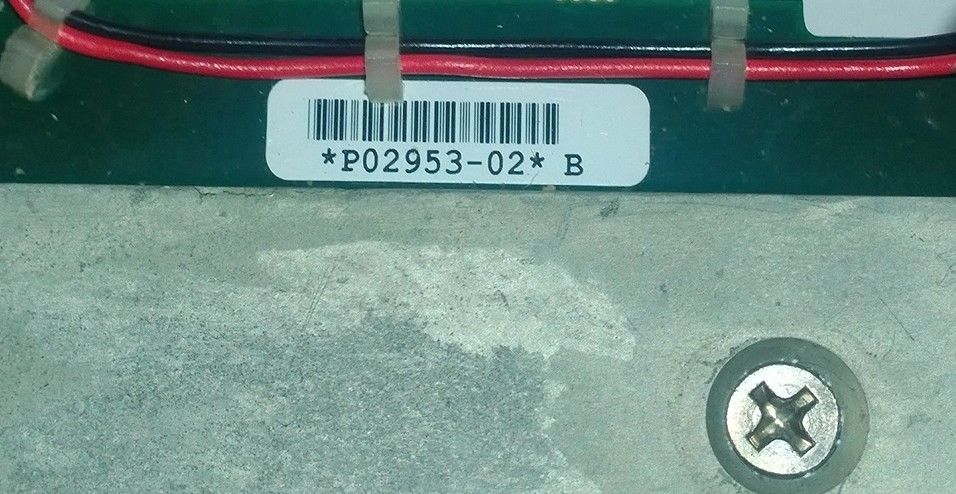

SONOSITE TITAN PORTABLE ULTRASOUND (w242)

Sale price$ 6,888.00